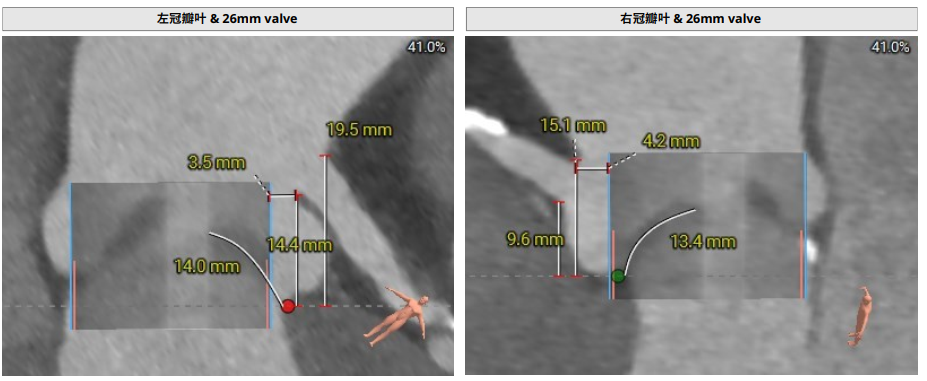

使用26mm瓣膜进行术前模拟;

LCA:16.3mm;RCA:14.4mm,法式窦空间大,考虑冠脉风险低;

瓣叶增厚,轻度钙化;

对合缘对齐(Commisure Alignment)角度为108°;室间隔膜部长2.2mm;

法式窦空间大;STJ高度21.5mm,均径32.9mm;升主动脉增宽,40mm处均径42.0mm,最宽处约45.5mm;心脏角度53°;